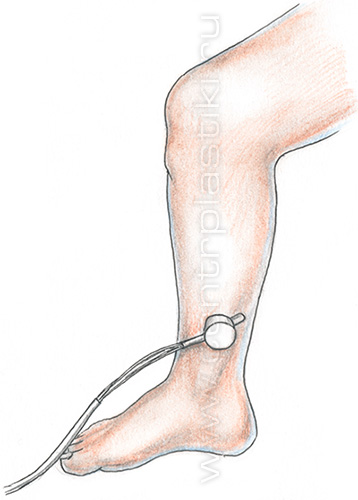

Резиновый жгут накладывают на верхнюю треть бедра так, чтобы сохранялась артериальная пульсация. При этом больной лежит. Выполняется бинтование ноги от стопы до жгута, пациент встает и ходит в течение получаса. Нормой является хорошая проходимость по глубоким венам бедра, которую можно выявить по отсутствию распирающей боли. Если боль ощущается, значит, отток затруднен, и требуется более детальное обследование.

Диагностировать затрудненность оттока можно и другим способом – рекомендовав пациенту постоянно носить компрессионный трикотаж. Если венозный отток от этого улучшится, а неприятные ощущения не появятся, значит, проходимость вен удовлетворительная. Если же пациент будет чувствовать боль, значит, отток все-таки затруднен.